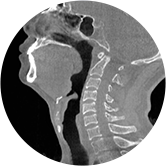

• 气道

• 颈椎

• 腰椎

气道三维影像重建